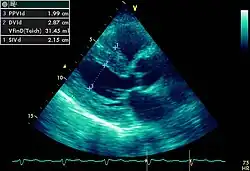

FIGURA 10

Heart left ventricular hypertrophy sa

Hipertrofia ventricular esquerda é o espessamento da parede do ventrículo esquerdo. Apesar de encontrarmos no electrocardiograma sinais eléctricos de hipertrofia o seu estudo é feito pormenorizadamente em ecocardiografia.[1]